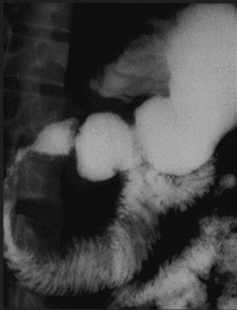

- Şişlərin əsas yerləşmə yeri qastrinoma (Wipple) bölgəsidir (12 bb və mədəaltı vəzinin başı.

- Qastrinomaların təxminən yarısı 12bb-da, digər hissəsi isə mədəaltı vəzidə tapılır.

- Xoraəleyhinə standart müalicəyə tabe olmayan və ya müalicədən həmən sonra təkrarlayan xora

- Postbulbar xoraları (12bb-ın II, III, IV hissələri, acı bağırsaq xoraları)

- Mədə və 12bb-da çoxlu xoralar